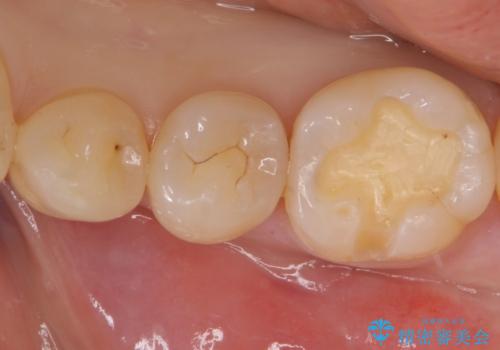

- 奥歯の樹脂の色が気になるとのことで来院されました。

変色しない材料での治療をご希望されたためセラミックインレーでの治療をしていくこととなりました。

継ぎ接ぎになった樹脂の詰め物から一塊のセラミックインレーに置き換えることで着色や二次う蝕のリスクを抑えます。